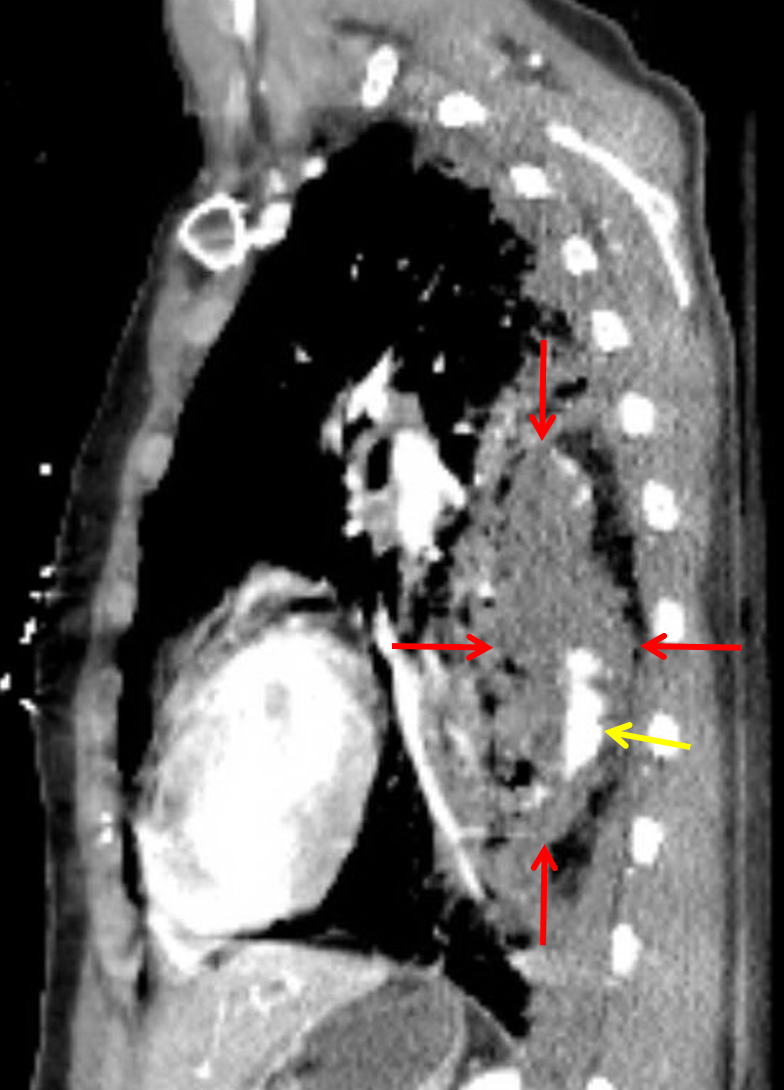

Age: 35

Sex: Female

Indication: Trauma

Sample ReportExtensive left pulmonary laceration with a focal intraparenchymal hematoma, predominantly involving the left lower lobe, and evidence of active internal bleeding.

Small left hemopneumothorax with apically directed left thoracostomy tube in place.